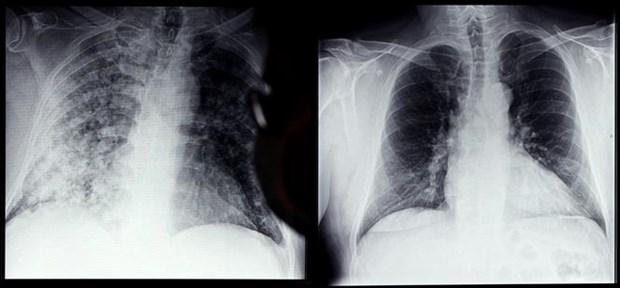

Trong số các bệnh nhân đi khám hậu COVID-19, chiếm tỷ lệ cao nhất, tới 60-70% là các trường hợp gặp các triệu chứng hô hấp. Triệu chứng cơ năng như mệt mỏi hụt hơi kéo dài hoặc gặp những sang chấn tâm lý lo âu mất ngủ sau COVID-19 cũng thường gặp.